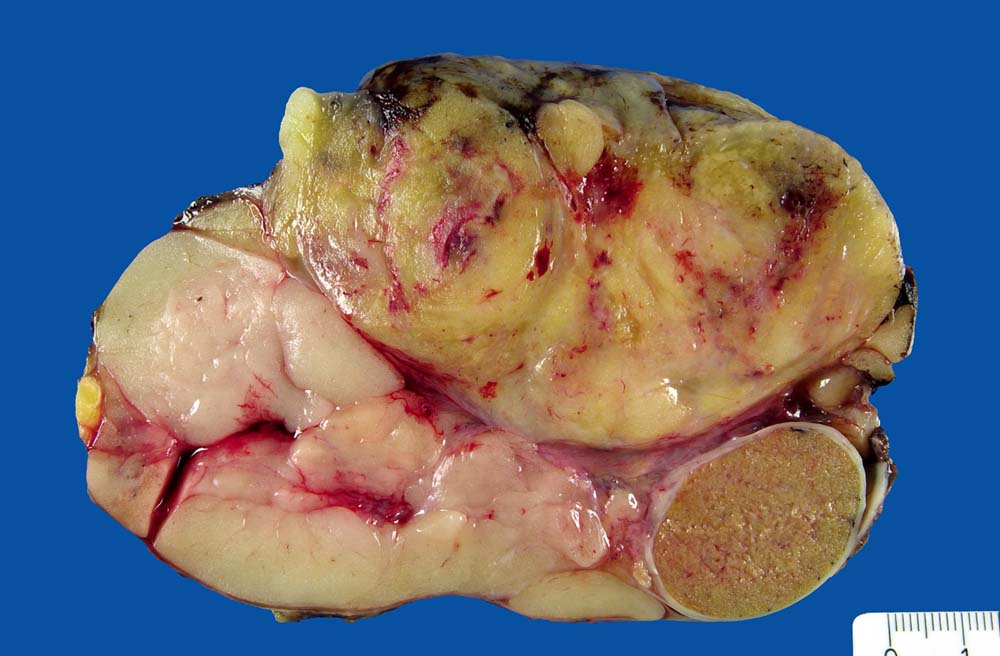

Makroskopie

Befund

Pathologischer Befund